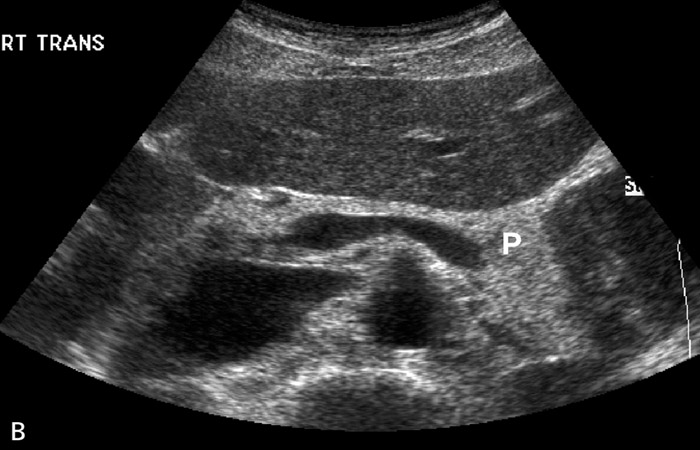

Η απεικόνιση του παγκρέατος παρέχει στοιχεία όσον αφορά την υφή του οργάνου και την παρουσία εστιακών βλαβών (ψευδοκύστεις, συμπαγείς εξεργασίες).